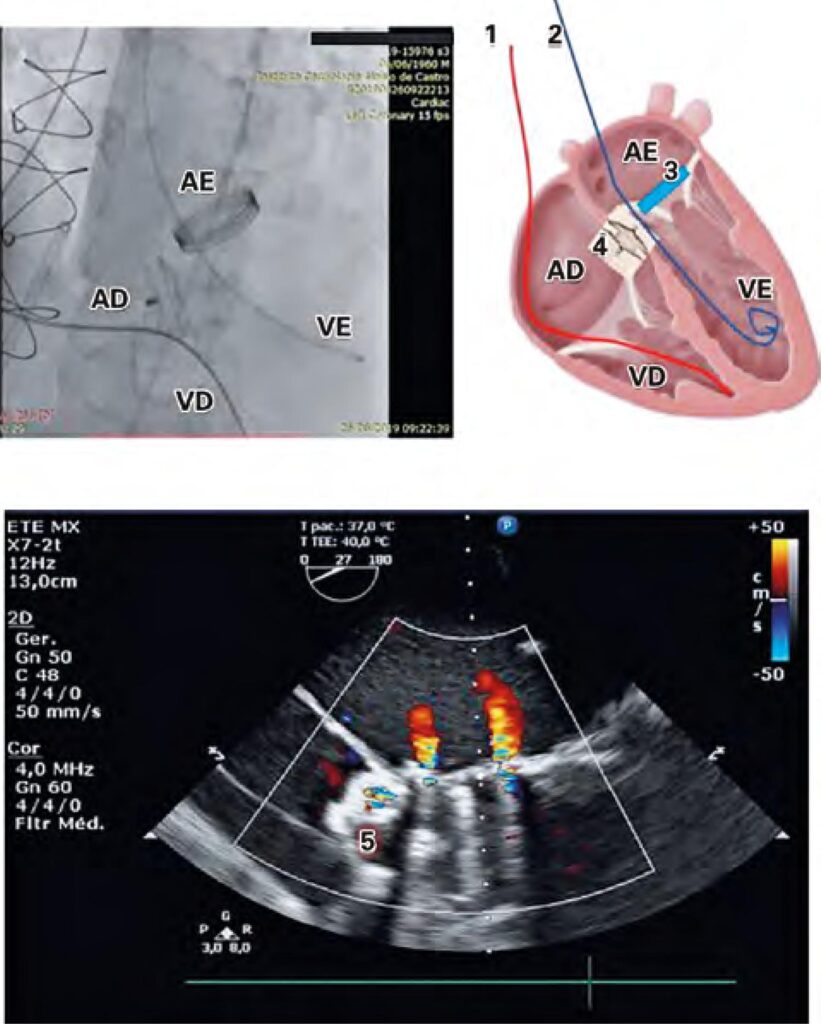

Figura 2

Esquema demonstrando a oclusão do defeito de Gerbode, o Amplatzer™ Septal Occluder e o Doppler do fluxo átrio direito-ventrículo esquerdo pós-procedimento. (1) Linha vermelha: eletrodo de marca-passo previamente implantado. (2) Linha azul: cateter pigtail posicionado no ventrículo esquerdo. (3) Representação esquemática da prótese valvar metálica em posição mitral. (4) Representação esquemática da prótese de comunicação interatrial implantada no defeito de Gerbode. (5) Doppler após fechamento do defeito.

AE: átrio esquerdo; VE: ventrículo esquerdo; VD: ventrículo direito; AD: átrio direito.